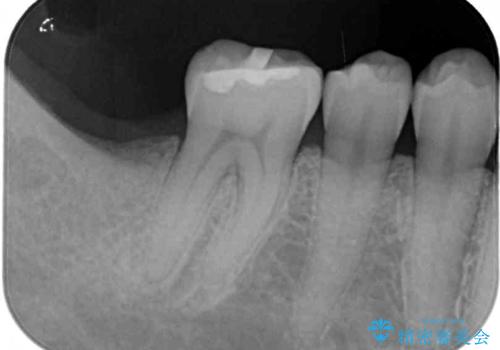

抜歯されたままの奥歯 ストローマンインプラントによる欠損補綴治療

- 抜歯してから放置されている右下の奥歯へのインプラント治療を希望して来院された患者様です。

世界中で高い信頼を得ているストローマンインプラントを用いて治療を行うこととしました。

ストローマン社のSLActiveというインプラントを使用し、インプラント埋入からクラウンが装着されるまで3ヶ月弱という短期間で終えることができました。